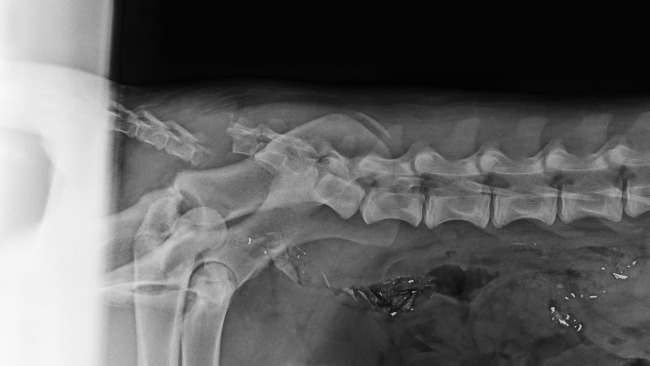

16 stycznia otrzymaliśmy zgłoszenie o potrąconym owczarku niemieckim leżącym na drodze w jednej z okolicznych wsi. Sprawca potrącenia odjechał z miejsca wypadku nie udzielając zwierzęciu pomocy. Dopiero inny kierowca, zauważywszy psa, zatrzymał się i zadzwonił do nas. Ruszyliśmy natychmiast nie wiedząc, w jakim stanie jest pies, ile bólu już zniósł i czy zdążymy na czas. Na miejscu naszym oczom ukazał się, leżący na poboczu drogi, piękny, młody psiak. Jamal cierpiał w milczeniu, ale wykonane w lecznicy zdjęcie RTG nie pozostawiło złudzeń — złamana kość biodrowa, kość łonowa, a do tego poważne uszkodzenie ogona.

Każdy ruch musiał sprawiać mu ogromny ból. Jamal dostał leki przeciwbólowe i antybiotyki, ale było jasne, że to dopiero początek długiej walki. Po konsultacji z lekarzami zapadła decyzja: operacja jest jedyną szansą, aby Jamal mógł znów chodzić i żyć bez bólu.

Zabieg odbył się 20 stycznia 2026 roku. Niestety, mimo starań lekarzy, ogona nie udało się uratować Psiak spędził noc w klinice. Teraz Jamal jest już pod naszą troskliwą opieką, ale przed nim długie tygodnie rekonwalescencji, rehabilitacji i specjalistycznego leczenia. To wszystko jest konieczne, aby mógł odzyskać sprawność i nadzieję na normalne życie.